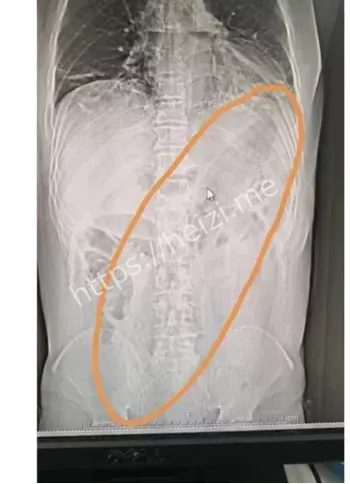

重点来了,这茄子可不是一般的茄子,30cm长,卡在直肠里,取出来可费了医生老大劲!据说大叔疼得满头大汗,医生也是满脸问号,手术室里气氛一度尴尬到爆。网友们在网上吵翻了,有人好奇“咋塞进去的”,有人直呼“这操作太野了”!还有人脑洞大开,猜是不是大叔在家做啥“实验”失败了? 直肠藏30cm茄子这关键词,绝对是热搜榜的潜力股。网友们一边吃瓜一边吐槽,纷纷表示这事儿太离谱,简直刷新认知底线。但说真的,这背后到底是啥情况?